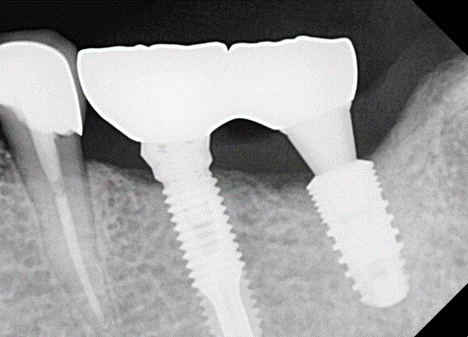

대구치부, 특히 7번 싱글은 위험하다. 또한 6번 심을 때 M-D distance(앞-뒤 폭경)가 12mm 쯤 나와서 2개의 픽스쳐는 못 심고 한 개 심어서 해결하는 경우에 특히

조심해야 한다.

픽스쳐도 찢어질 수 있고, 어벗먼트도 부러질 수 있다. 또한 나사 풀림도 많이 발생한다. 이런 특별한 경우에도 EZC와 같은 convertible abutment가 유리하다.